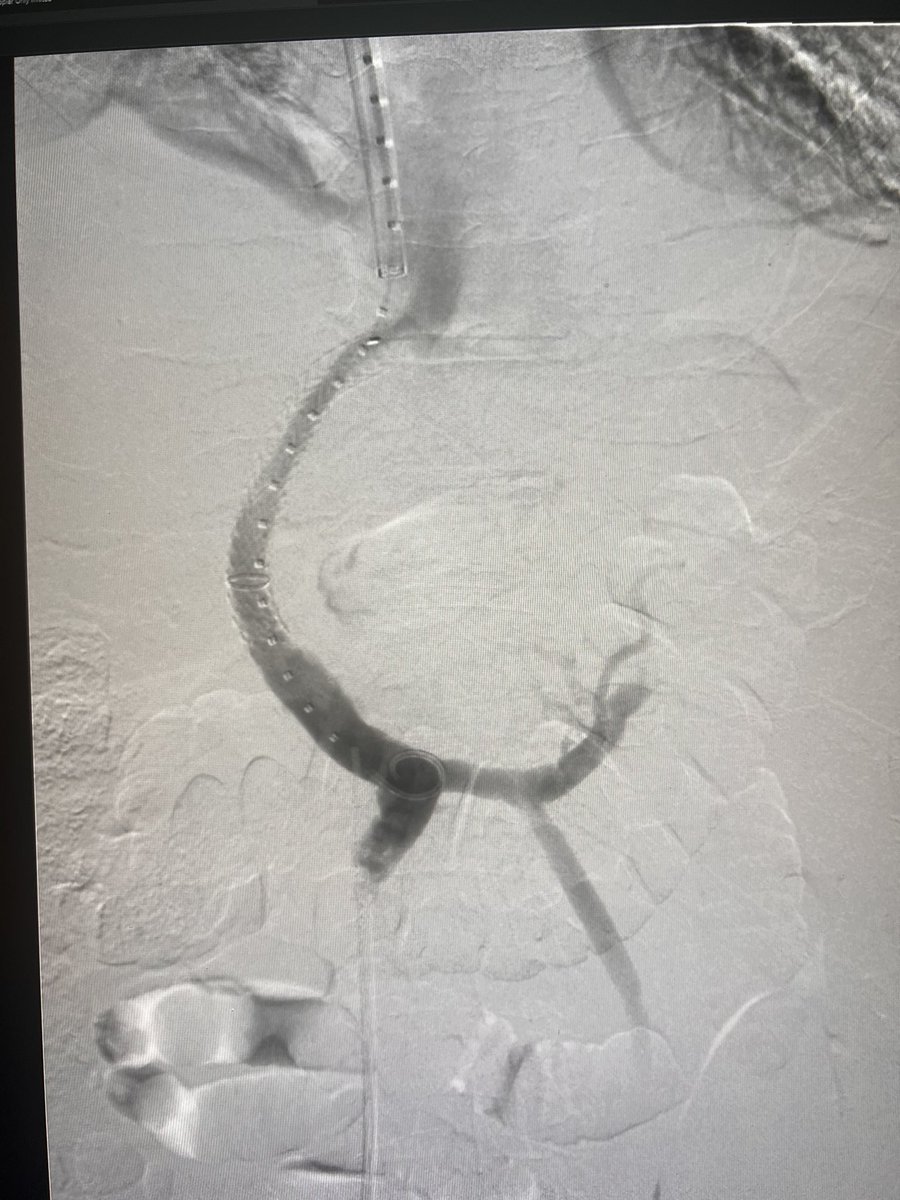

1/ Right innominate stenosis..how would you approach this? 🙋🏽♂️R radial for the filter 💪🏽R brachial for crossing and stent 🦵🏾R femoral for imaging “Before anything else, preparation is the key to success” #CardioX #IRAD #VascTwitter #Cardiotwitter #PAD RadialFirstBot